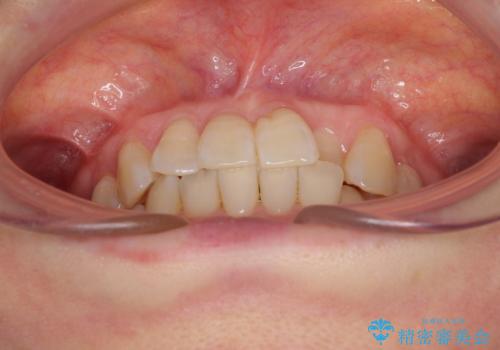

前歯のクロスバイト インビザライン矯正で改善

- むし歯治療を契機に、長年気にしていた前歯のクロスバイトの改善を希望された患者様です。

汚れが溜まりやすく、歯ぎしりがうまくできないため、インビザラインを用いて矯正治療を行うこととしました。

インビザラインによる前歯のクロスバイトの改善は、治療期間中に前歯でしか咬めない時期が続いたり、歯肉退縮や歯髄壊死のリスクが高まったりと、治療中にトラブルを抱えることがあります。

特に上顎側切歯(真ん中から2番目の歯)が舌側に引っ込んでいるケースは、インビザラインでは改善しきれないことがあると言われています。